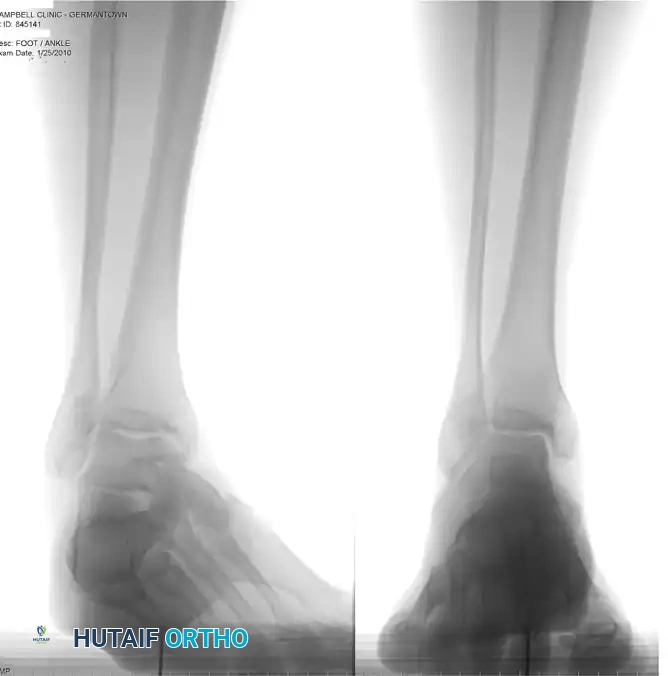

Standard weight-bearing radiographs of the foot and ankle are required to assess for structural malalignment (e.g., varus hindfoot), avulsion fractures of the fibula (fleck sign), and the morphological status of the os peroneum.